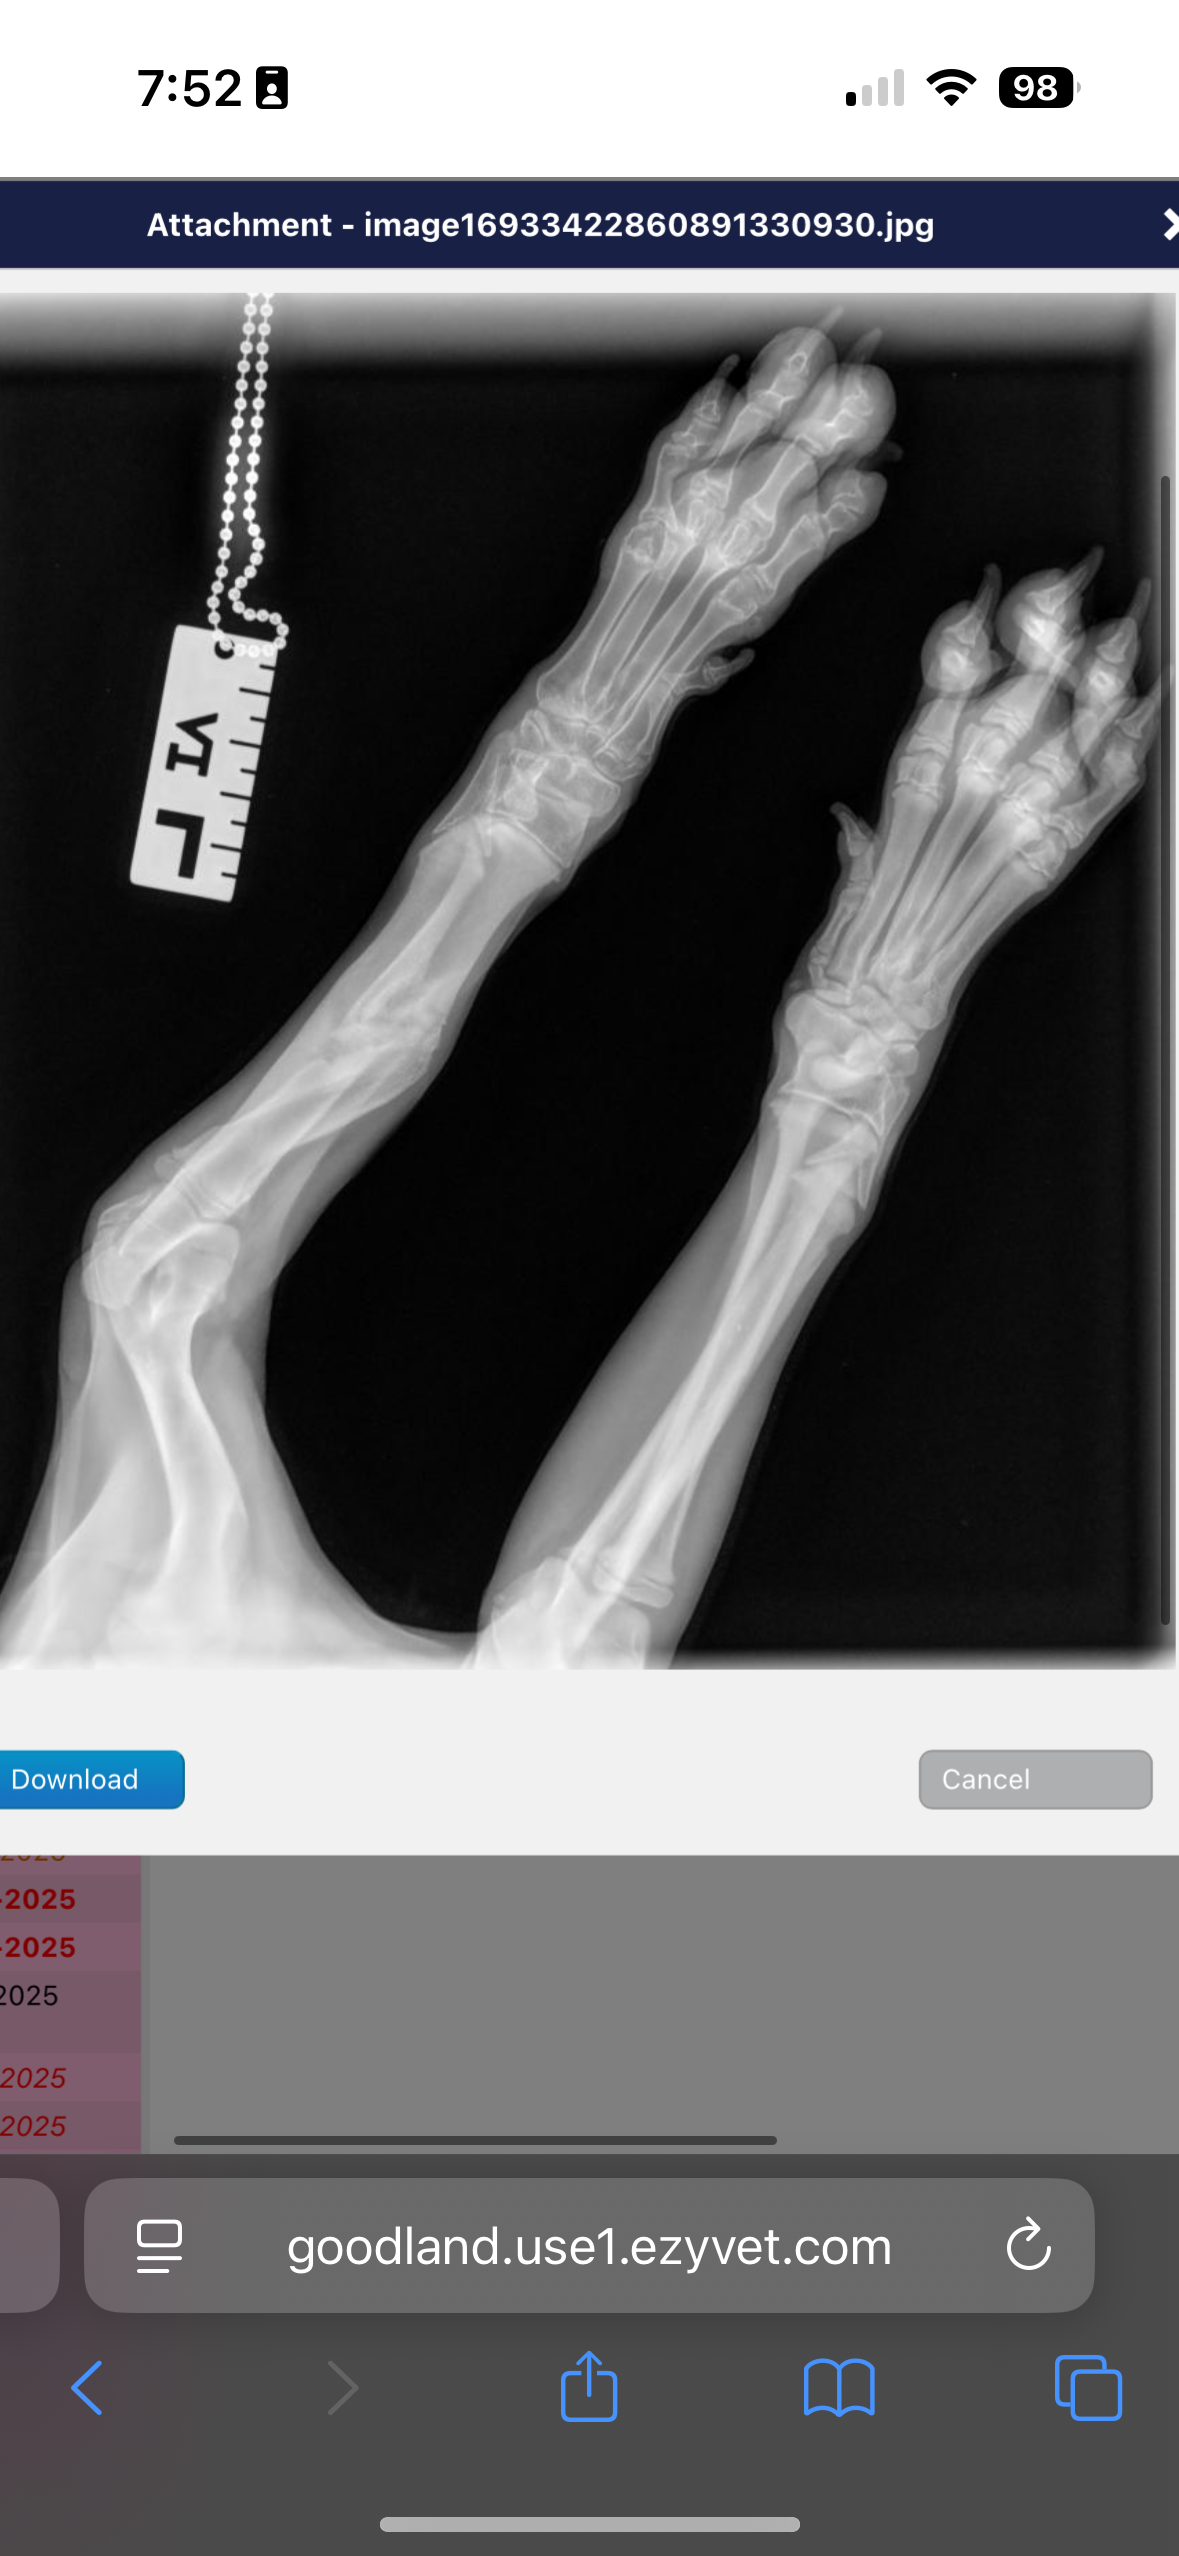

Sweet baby Jelly Bean came to us recently and we immediately knew something wasn’t right with her front leg. So we did what anyone would do, and took her to the vet. JB’s front left leg had a break in it at some point, and now needs surgery on her elbow to fix it. Our only other choice is to amputate her leg. ☹️

Jelly Bean needs something called a “proximal releasing ulner oscteotomy”… which is a really fancy way of saying elbow surgery. In growing dogs, the bones in the forelimb might grow at different rates. Jelly is only (almost) 4 months old. Because of the trauma in her leg, one bone is growing faster than the other. It is creating abnormal joint stress in her elbow.